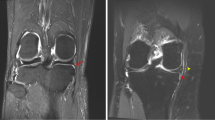

De Smet AA, Norris MA, Yandow DR, Quintana FA, Graf BK, Keene JS. MR diagnosis of meniscal tears of the knee: importance of high signal in the meniscus that extends to the surface. AJR Am J Roentgenol. 1993;161(1):101–7. https://doi.org/10.2214/ajr.161.1.8517286.

Jee WH, McCauley TR, Kim JM, Jun DJ, Lee YJ, Choi BG, et al. Meniscal tear configurations: categorization with MR imaging. AJR Am J Roentgenol. 2003;180(1):93–7. https://doi.org/10.2214/ajr.180.1.1800093.

Shakespeare DT, Rigby HS. The bucket-handle tear of the meniscus. A clinical and arthrographic study. J Bone Joint Surg Br. 1983;65(4):383–7. https://doi.org/10.1302/0301-620X.65B4.6874707.

Pache S, Aman ZS, Kennedy M, Nakama GY, Moatshe G, Ziegler C, et al. Meniscal root tears: current concepts review. Arch Bone Jt Surg. 2018;6(4):250–9.